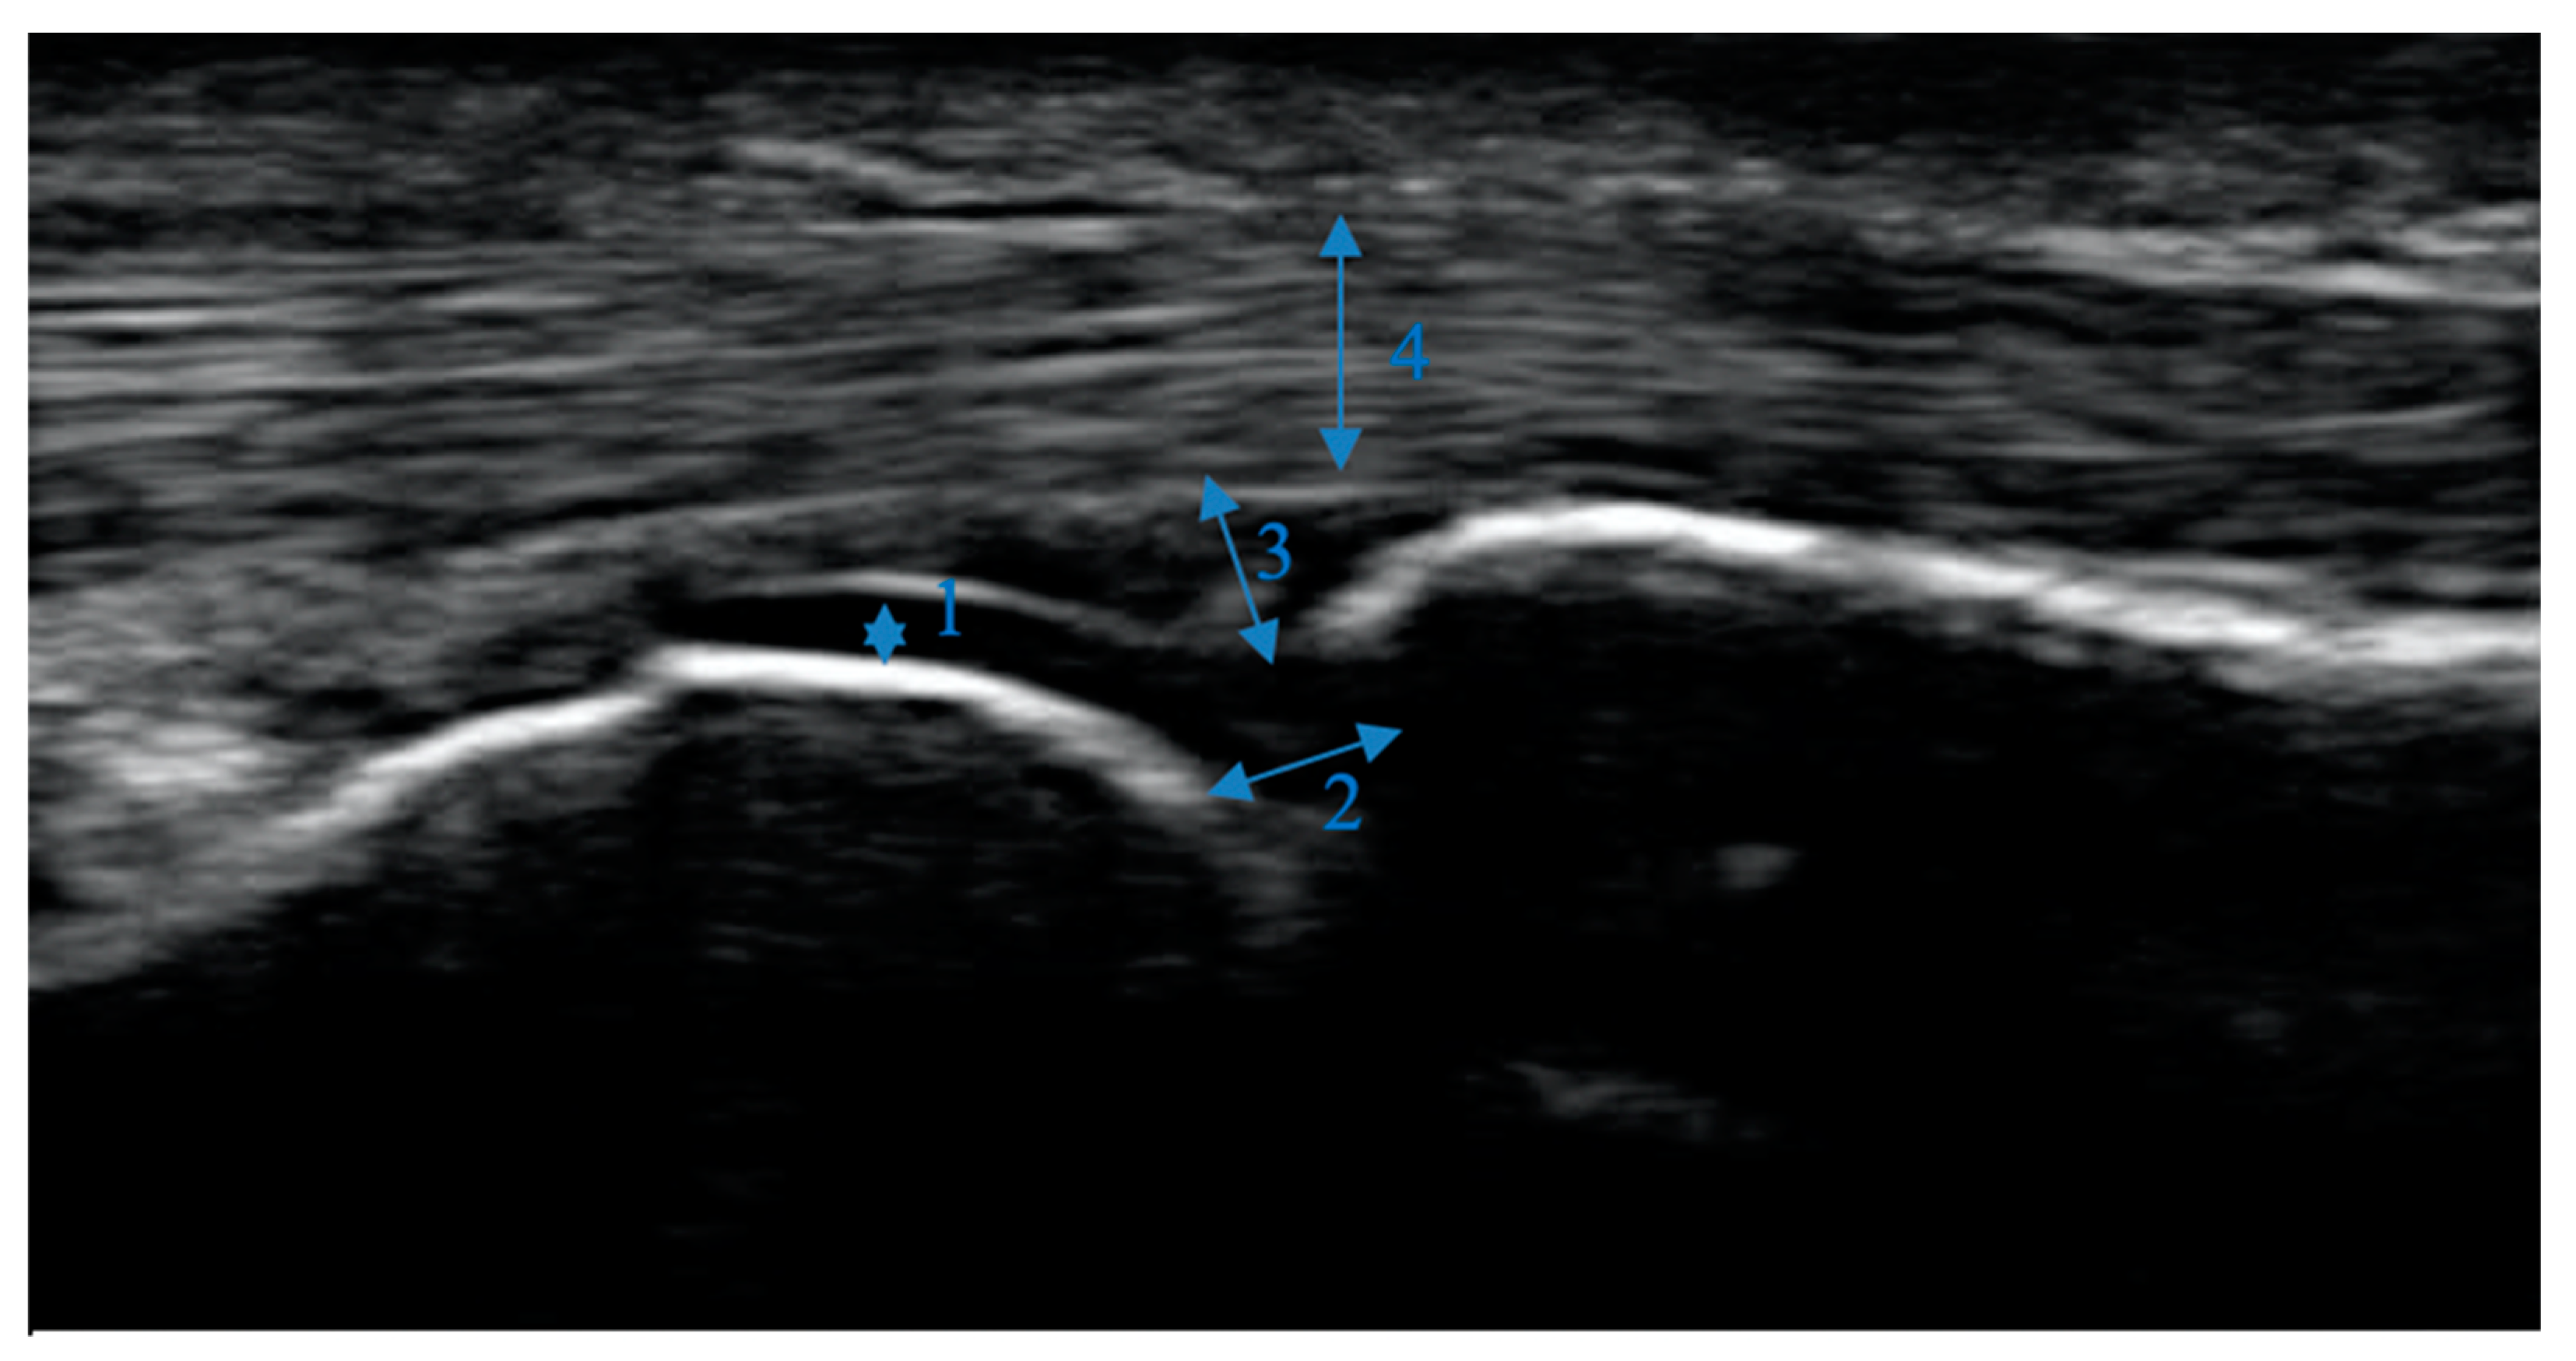

To read the images, a modified (palmar, not dorsal view) semi-quantitative score for osteophytes ranging from 0-3: 0 = no osteophytes, 1 = mild osteophytes, 2 = moderate osteophytes and 3 = severe osteophytes was used. An increase in the score describes an increase in the severity of the osteophytes found. The biggest osteophyte at each joint was scored. The score was previously described by Keen et al., Kortekaas et al., Mathiessen et al. and was evaluated and recommended by the Outcome measures in Rheumatology ultrasonography (OMERACT) group [9,10,11,12,13]. If one or more joints of the participant showed osteophyte values ≥1, they were positively defined of showing HOA signs. The pictures were scored by a medical student (MG) in a consensus read with an experienced rheumatology resident (PS). Figure 1 shows a normal MCP joint without any major pathologies. Figure 2 shows an example of the different grades of osteophytes for each joint group in palmar view.

Figure 1. Normal MCP joint: Bone surface is regular and hyperechoic. The cartilage is homogeneously anechoic and limited cranially by a white band (1). Joint space is partly visible (2). The joint capsule is not widened (3). There is an adequate amount of synovial fluid in the capsule. The tendons (4) run across the joint and are homogeneously isoechoic.